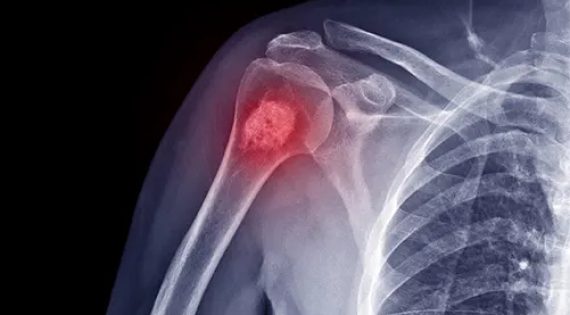

Οι ανευρυσματικές οστικές κύστεις (ABCs) είναι καλοήθεις αλλοιώσεις στα οστά

Το χονδροσάρκωμα είναι ένας κακοήθης (καρκινικός) όγκος των οστών που αποτελείται από κύτταρα που παράγουν χόνδρο.